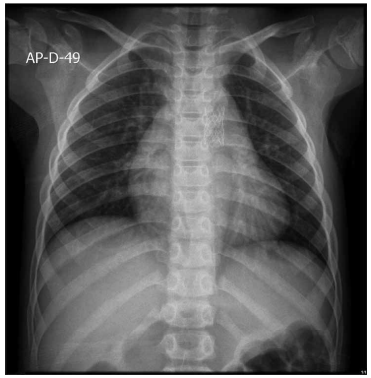

Paciente de 1 ano e 11 meses deu entrada no Pronto-

-Socorro com história de ânsia de vômito, palidez, sudorese e cianose ontem, sem perda de consciência. Hoje,

refere novo quadro de cianose e palidez com saturação

de 65% em ar ambiente, segundo aferição com o aparelho da mãe. Na avaliação atual, a saturação periférica da

criança em ar ambiente foi de 95%. Mãe refere que, com

3 dias de vida, teve diagnóstico de cardiopatia congênita

e bloqueio atrioventricular total, necessitando de implante de marca-passo definitivo, além de quadro convulsivo

(segue com neurologista), mas nunca havia ficado roxa

antes. Qual é a cardiopatia congênita provável associada

ao bloqueio atrioventricular? Considere a radiografia de

tórax atual a seguir.

(Arquivo pessoal; imagens usadas com autorização)